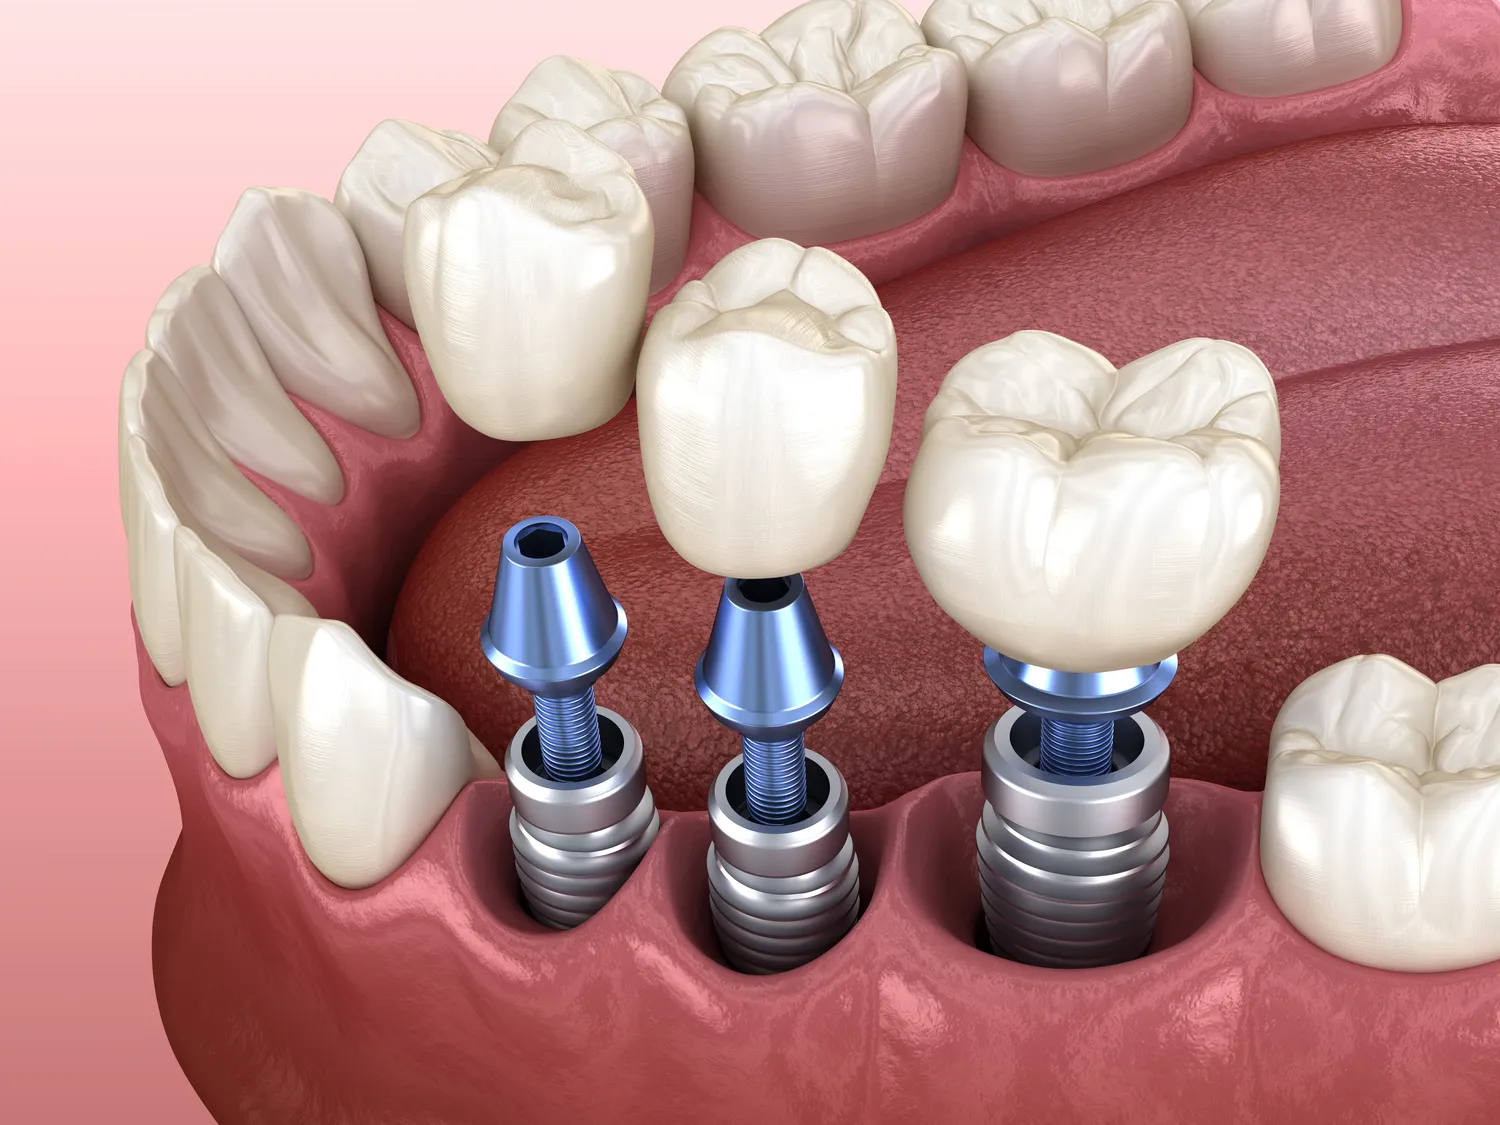

Proces zakupu implantów dentystycznych w Szczecinie składa się z kilku kluczowych etapów, które mają na celu zapewnienie pacjentowi jak najlepszej opieki i efektu końcowego. Pierwszym krokiem jest zazwyczaj konsultacja ze specjalistą, podczas której lekarz ocenia stan zdrowia jamy ustnej pacjenta oraz przeprowadza niezbędne badania diagnostyczne. Na podstawie tych informacji lekarz przedstawia plan leczenia oraz omówi dostępne opcje implantologiczne. Kolejnym etapem jest przygotowanie do zabiegu, które może obejmować dodatkowe procedury takie jak ekstrakcja zębów czy leczenie chorób przyzębia. Sam zabieg wszczepienia implantu odbywa się najczęściej w znieczuleniu lokalnym i trwa od jednej do kilku godzin, w zależności od skomplikowania przypadku. Po wszczepieniu implantu następuje okres gojenia, który może trwać od kilku tygodni do kilku miesięcy, a następnie konieczne jest zamocowanie korony protetycznej.

W ostatnich latach implantologia znacznie się rozwinęła, a nowoczesne technologie wprowadzają innowacje, które poprawiają komfort oraz efektywność zabiegów. W Szczecinie wiele klinik korzysta z zaawansowanych metod, takich jak cyfrowe planowanie zabiegów, co pozwala na precyzyjne dopasowanie implantu do indywidualnych potrzeb pacjenta. Dzięki technologii skanowania 3D możliwe jest uzyskanie dokładnych obrazów jamy ustnej, co ułatwia lekarzom podejmowanie decyzji oraz minimalizuje ryzyko powikłań. Kolejnym ważnym osiągnięciem jest stosowanie materiałów biokompatybilnych, które zmniejszają ryzyko odrzutu implantu przez organizm. Wiele klinik w Szczecinie oferuje również techniki takie jak wszczepienie implantów natychmiastowych, które pozwalają na umieszczenie implantu w tym samym dniu, co ekstrakcja zęba. Takie podejście znacząco skraca czas leczenia i przyspiesza proces odbudowy uzębienia.

Decyzja o wszczepieniu implantów dentystycznych wiąże się z wieloma korzyściami, ale także pewnymi wadami, które warto rozważyć przed podjęciem ostatecznej decyzji. Do głównych zalet należy trwałość i funkcjonalność implantów, które mogą służyć przez wiele lat, a nawet dekad. Implanty nie tylko poprawiają estetykę uśmiechu, ale również przywracają pełną funkcjonalność żucia, co ma kluczowe znaczenie dla jakości życia pacjenta. Dodatkowo, wszczepienie implantu może zapobiegać utracie kości szczęki, która często występuje po utracie zębów naturalnych. Z drugiej strony, istnieją również pewne wady związane z tym zabiegiem. Koszt implantów może być znaczny, co dla niektórych pacjentów stanowi barierę finansową. Ponadto, proces gojenia po wszczepieniu implantu wymaga czasu i cierpliwości, a niektórzy pacjenci mogą doświadczać bólu lub dyskomfortu po zabiegu. Istnieje również ryzyko powikłań, takich jak infekcje czy problemy z integracją implantu z kością.